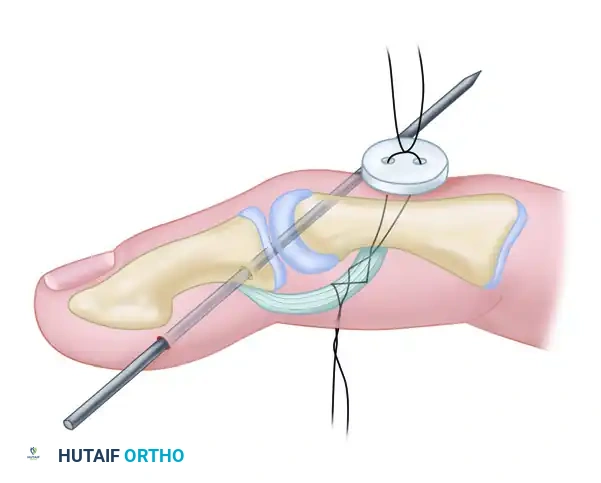

Technique of Tenodesis (Button and Pull-Out Wire)

When anchoring an extensor tendon to bone (e.g., distal phalanx avulsions, mallet finger reconstructions, or specific central slip repairs), a robust fixation method is required. The pull-out wire technique combined with Kirschner wire (K-wire) stabilization provides excellent biomechanical rigidity.

Surgical diagram illustrating the trajectory of tendon repair and the complex interplay of the dorsal apparatus during fixation.

Step-by-Step Surgical Protocol:

- Joint Stabilization:

Begin by reducing the joint to the desired anatomical position (usually full extension for mallet injuries or neutral for central slip repairs). Drive a smooth Kirschner wire (typically 0.035 or 0.045 inch) across the joint to neutralize deforming forces. The Kirschner wire is cut off beneath the skin at the points indicated by the surgical plan to prevent pin tract infections. - Bone Preparation:

Create a small cortical window or drill holes at the anatomical insertion footprint of the tendon using a micro-burr or fine drill bit. - Tendon Preparation (Bunnell Suture):

A pull-out technique using the Bunnell retrograde or the antegrade technique is usually required. Weave a heavy non-absorbable suture (or stainless steel wire, depending on surgeon preference and chronicity) through the distal stump of the tendon. - Passing the Suture:

With straight needles, thread the ends of the wires through the prepared bony holes. This action leads the tendon directly into the cortical opening. - Dorsal Button Fixation:

Pass the needles through the dorsum of the finger. Tie the sutures securely through a sterile surgical button over the middle or distal phalanx (depending on the zone of injury). The button distributes the pressure, preventing skin necrosis. - Pull-Out Wire Routing:

Bring the Bunnell pull-out wire through the volar surface of the finger. This allows for easy removal of the construct once bony healing or robust fibrous union has occurred. - Wound Closure:

Irrigate the wound copiously. Close the skin with 5-0 nylon in a simple interrupted or horizontal mattress fashion. Ensure the paratenon is approximated if possible to prevent skin adherence to the tendon.